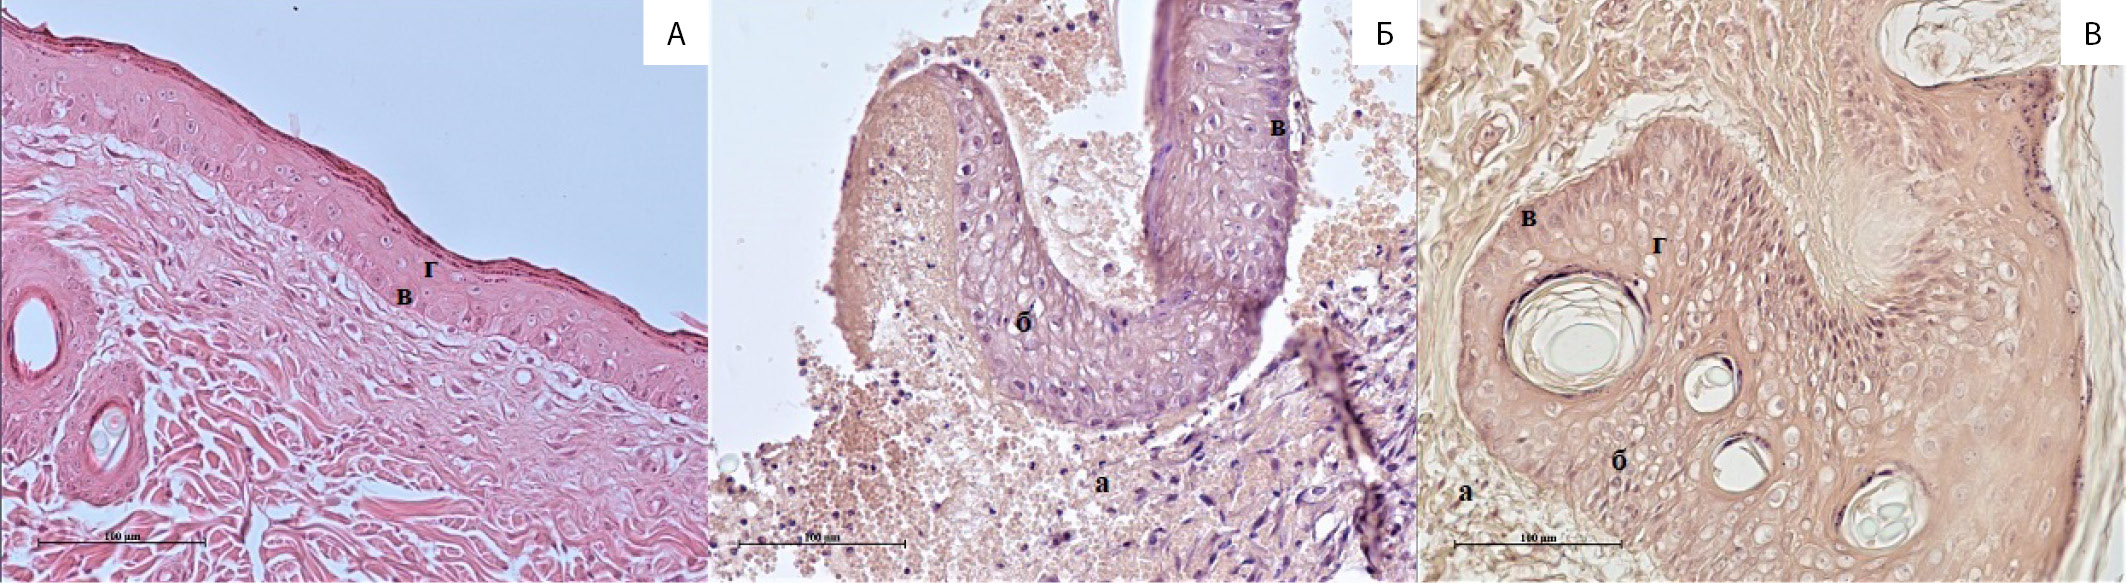

В коже интактных крыс, окрашенной гематоксилином и эозином, в гомотопичной области нанесения раны у экспериментальных животных четко визуализируются базальный, шиповатый и зернистый слои (рис. 2А, в и г). Раневые дефекты у крыс в группах СД и ЦБ не имеют видимых морфологических отличий в окрашенных гематоксилином и эозином срезах (рис. 2Б, 2В). На 8-е сутки после нанесения раны большую часть поверхности закрывает грануляционная ткань, обильно инфильтрированная нейтрофилами, макрофагами и лимфоцитами (а). Поверх нее располагаются некротические массы. Регенерирующий край эпителия утолщен за счет большого числа клеток (б). Визуально и по измеренной площади раны в двух группах в этот срок также не различались.

Рис. 2. Препараты кожи крысы, окраска гематоксилином и эозином, ×200. А – интактная кожа; Б – сахарный диабет, 8-е сутки заживления; В – группа цитратного буфера, 8-е сутки заживления; а – область воспаления и образования грануляционной ткани; б – регенерирующий край эпидермиса; в – базальный слой; г – шиповатый слой.